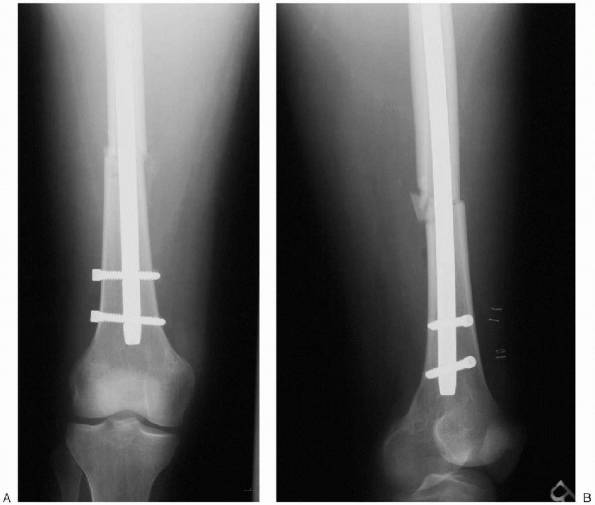

![]() |

|

FIGURE 36-25. A and B: Final postoperative radiographs.

manner. Before wound closure, fracture reduction and nail position,

including all locking screws, are assessed radiographically in the

sagittal and coronal planes (Fig. 36-25).